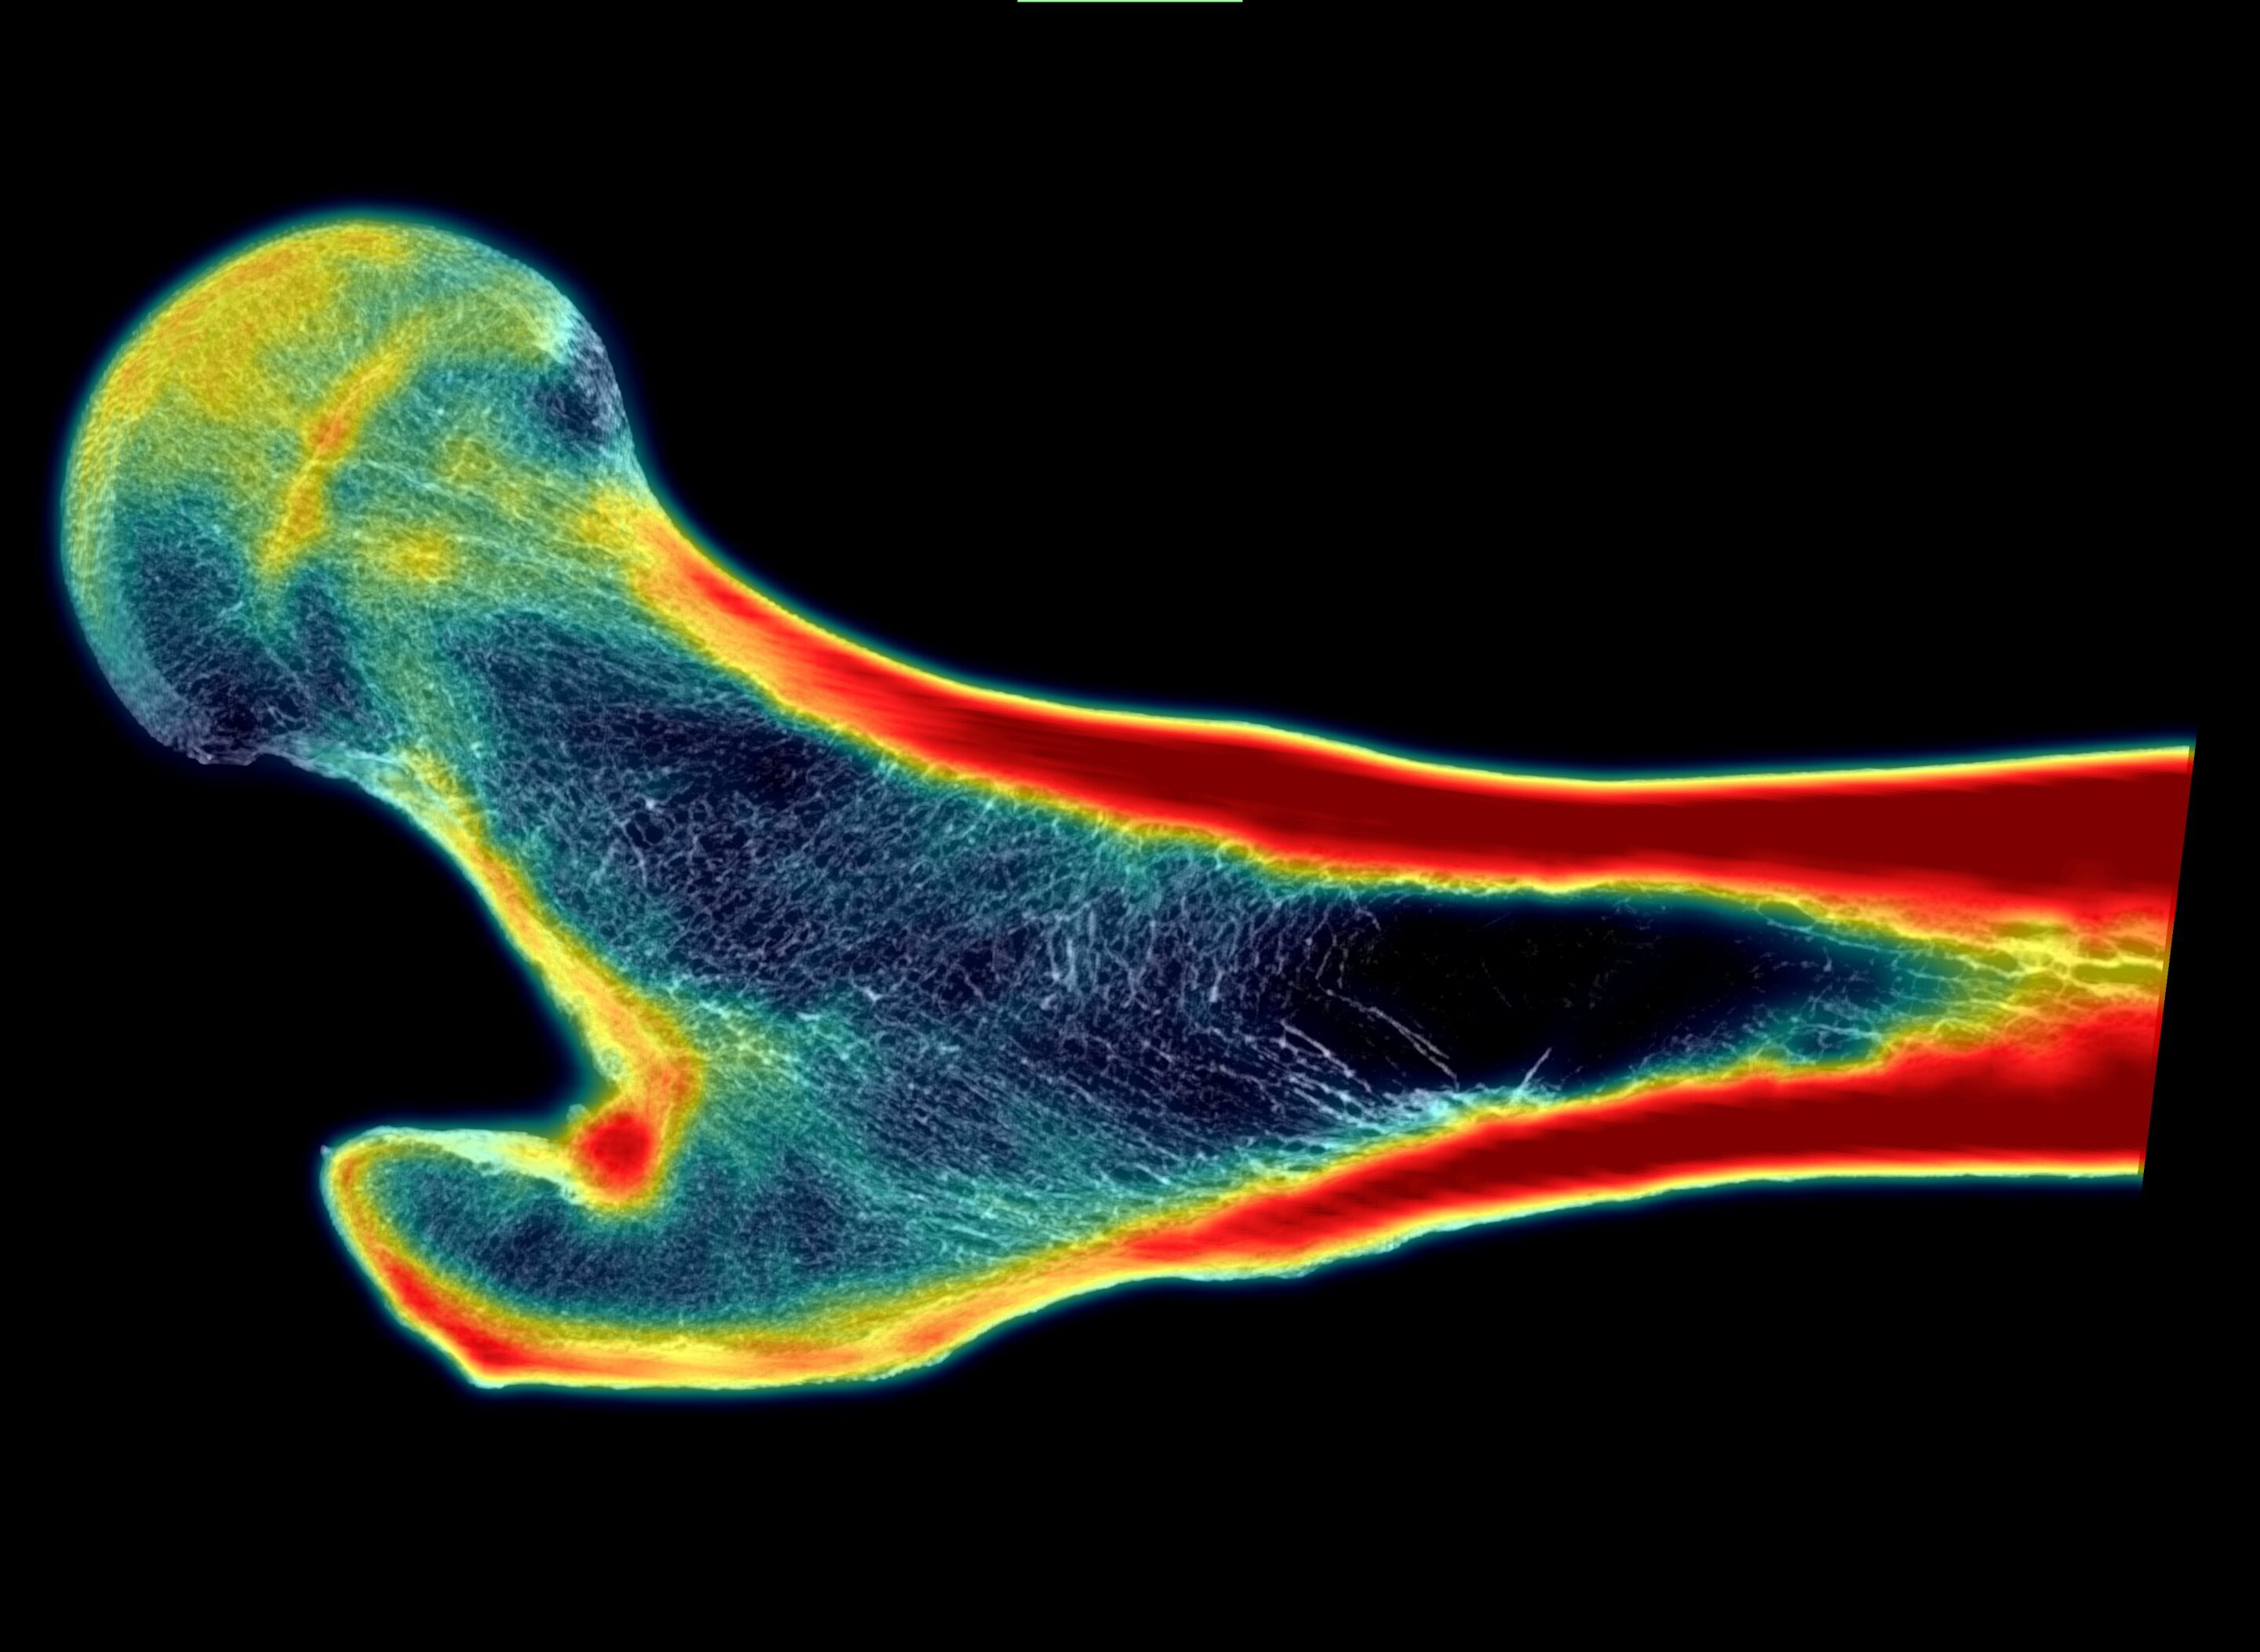

Ученые из Юго-западного исследовательского института (SwRI) разработали новую технологию, которая может значительно улучшить диагностику остеопороза и снизить риск переломов у пожилых людей. Метод основан на искусственном интеллекте (ИИ) и позволяет создавать изображения костей в высоком разрешении, которые детально показывают их внутреннюю структуру. Это помогает врачам точнее оценивать прочность костей и выявлять пациентов с высоким риском переломов.

В новом подходе используется глубинное обучение, которое обучает нейросеть восстанавливать высококачественные изображения из стандартных снимков. Это позволяет моделировать структуру кости и прогнозировать её прочность.